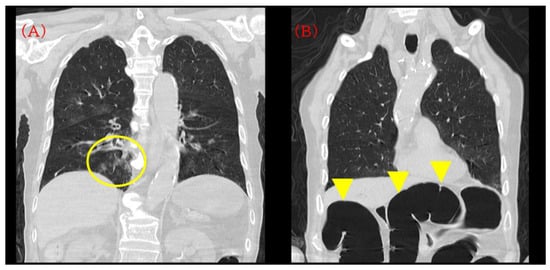

A portable anteroposterior chest radiograph obtained immediately after intubation confirmed appropriate endotracheal tube position and showed no new diffuse bilateral infiltrates suggestive of acute respiratory distress syndrome (ARDS) or marked progression of pneumonia. In contrast, the upper abdomen demonstrated markedly dilated gas-filled bowel loops consistent with colonic distension, likely involving the transverse colon (Figure 4). Following a discussion with the family, a do-not-resuscitate order was confirmed, CPR was discontinued at 05:44, and death was pronounced at 06:15. The death certificate listed acute heart failure as the immediate cause of death.

Figure 4.

Portable chest radiograph at the time of intubation on postoperative day 4. Yellow arrows indicate markedly dilated gas-filled bowel loops in the upper abdomen, consistent with colonic gas distension.

The anteroposterior bedside chest X-ray confirmed the appropriate position of the endotracheal tube and showed no new diffuse bilateral infiltrates suggestive of acute respiratory distress syndrome (ARDS) or marked progression of pneumonia. The upper abdomen shows markedly dilated gas-filled bowel loops, most prominent in the transverse colon region; although interpretation is limited on a portable chest radiograph, this finding is considered supportive of possible abdominal pathology in a clinical picture compatible with sepsis.